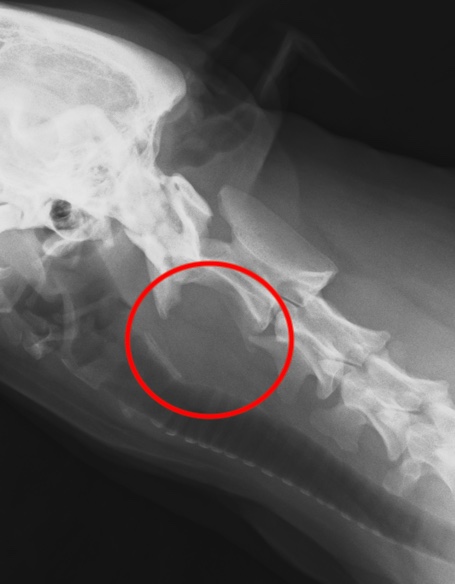

扁桃の扁平上皮癌がリンパ節転移したレントゲン画像(赤丸)